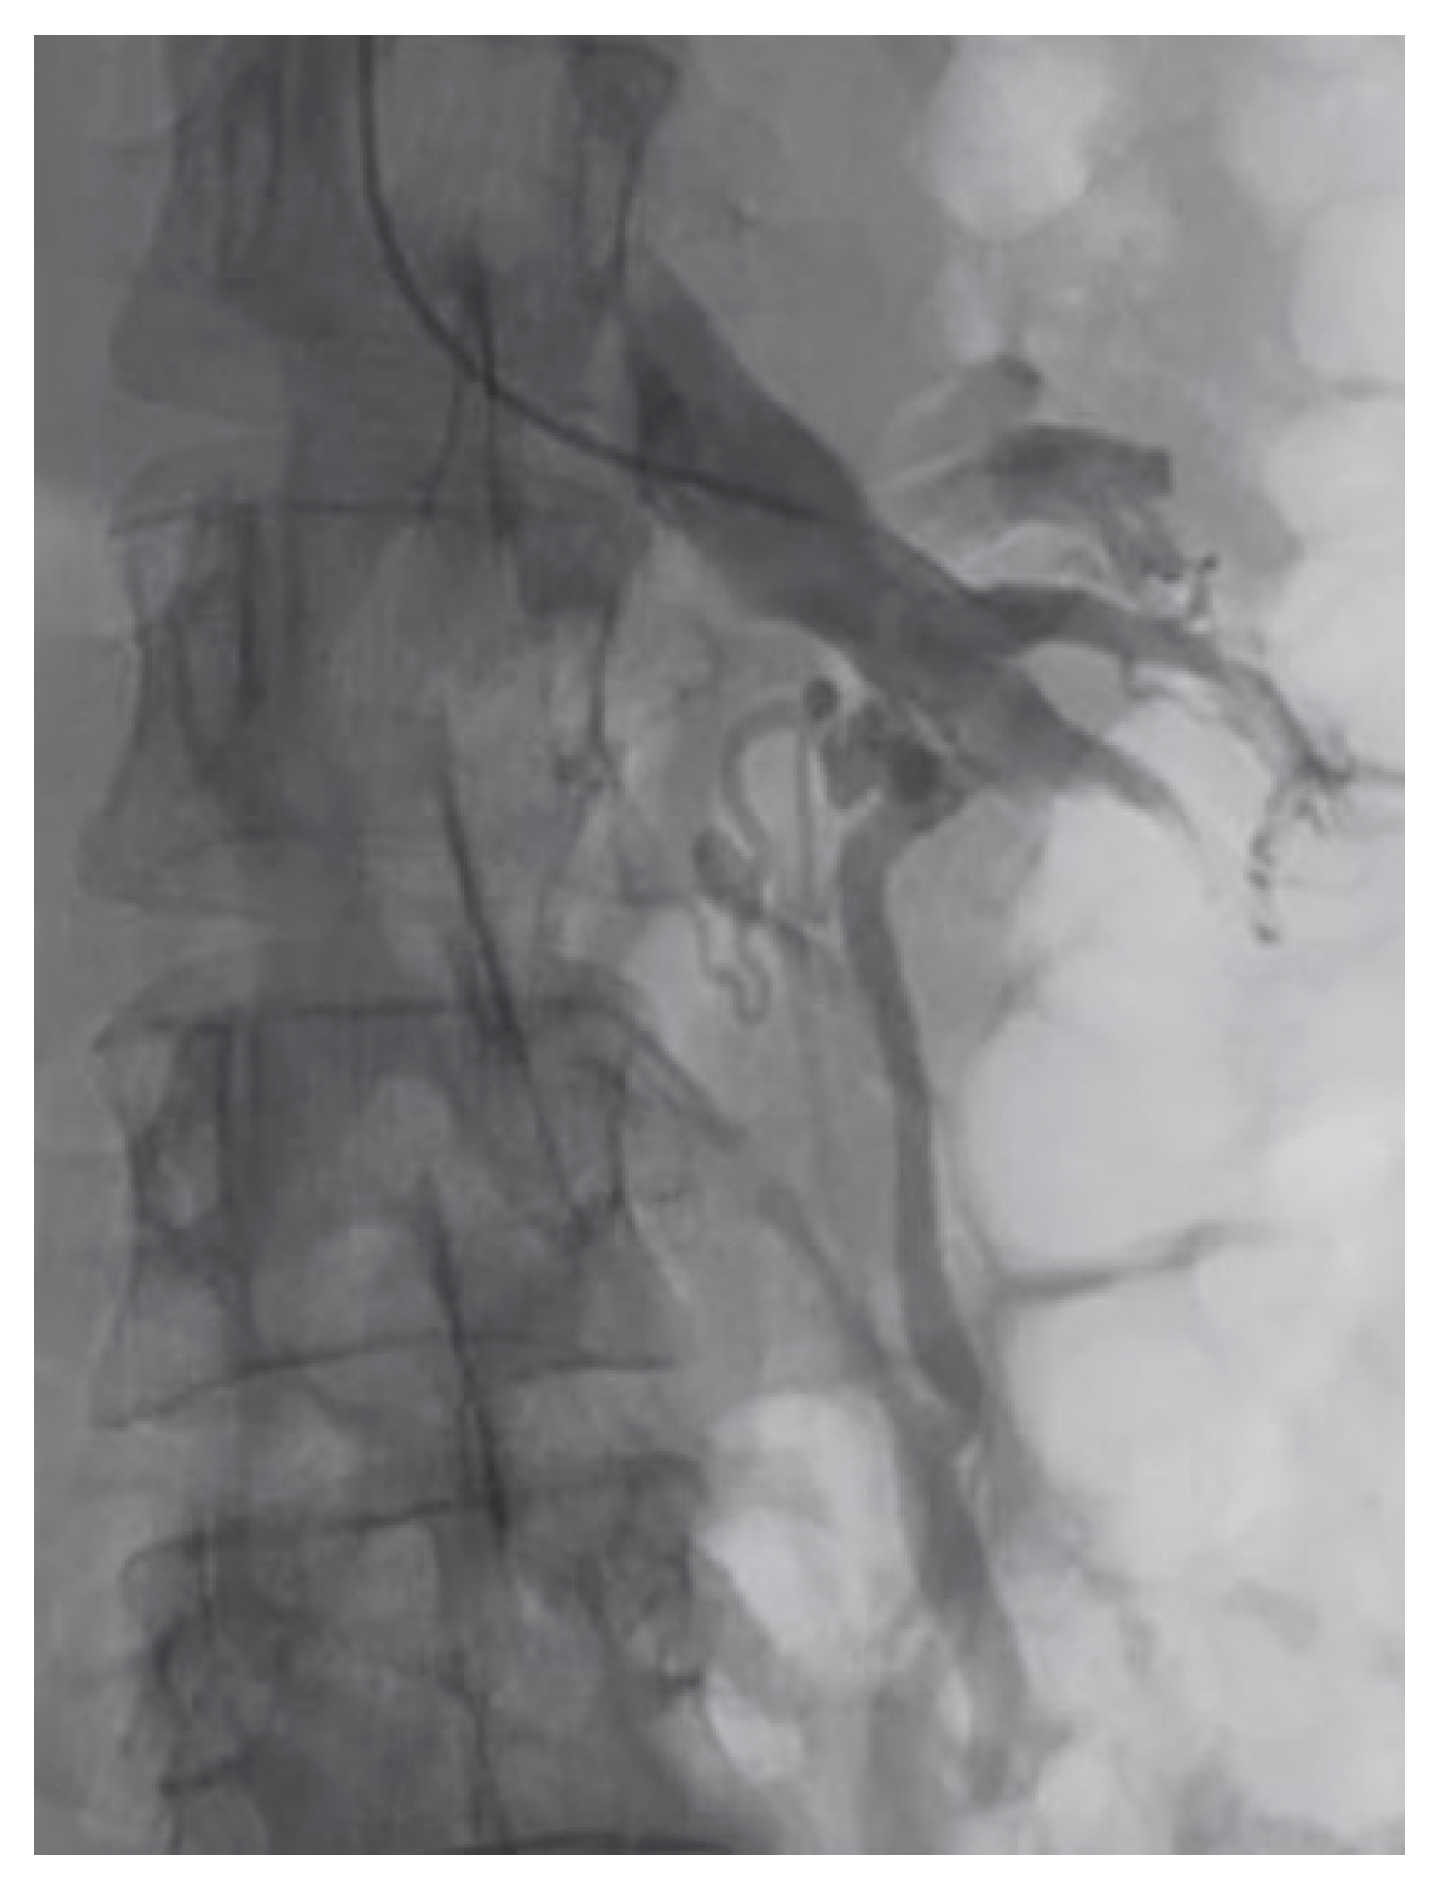

From Nutcracker Phenomenon to Nutcracker Syndrome: A Pictorial Review